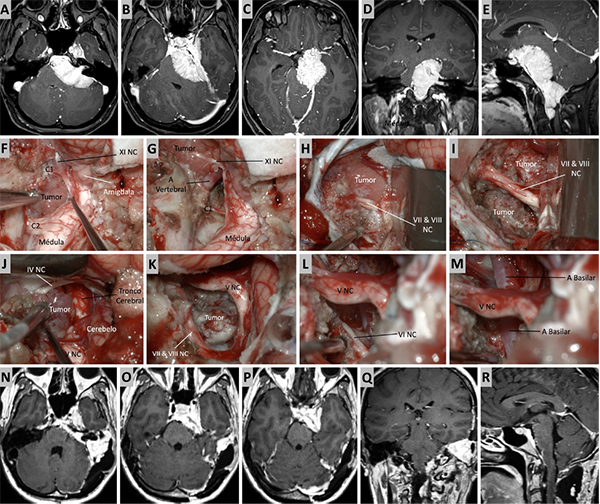

Figura 5. Caso ilustrativo #3. A-D. Resonancia que muestra MRPC con implantación clival. E-J. Se realiza un abordaje retrosigmoideo, consiguiendo la liberación del complejo VII-VIII del tumor y su resección completa. K-M. Resultado imagenológico postquirúrgico.

Figura 10. Caso ilustrativo #8. MRPC con implantación petroclival con invasión con extensión a la fosa media, clivus inferior, agujero magno y región premedula. Paciente con anacusia izquierda. A. Se observa un corte axial. MPC con extensión al ángulo pontocerebeloso y compromiso del CAI. B. Se observa extensión del tumor a la fosa media, seno cavernoso y ala mayor del esfenoides. C. Se observa extensión del tumor a ala menor del esfenoide, cisterna silviana y optocarotidea.D-E. Extensión del tumor a la fosa media, al clivus inferior y a la región premedular. Se realizo un abordaje presigmoideo acompañado de un abordaje far-lateral y un abordaje retrosigmoideo. F. Se observa la porción tumoral ubicada en el foramen magno y la región premedular, fue necesario un abordaje far-lateral. G. Resección completa de la porción ubicada en foramen magno y región premedular. H. Porción tumoral que se extiende desde clivus inferior a clivus medio. I-J. Resección de tumor de clivus medio e inferior. K. Porción tumoral en clivus superior con extensión a fosa media. Se realizo un abordaje transpetroso anterior para esta región. L-M. Resección casi total. N-R. Imágenes postquirúrgica que muestran una resección casi total.